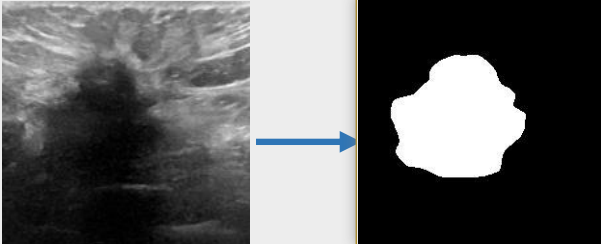

## 算法原理 U-KAN与其它图像分割算法一样,将图片数据送入模型后,依次通过预处理、特征提取,最后经过卷积预测出像素类别实现分割。

## 环境配置 ``` mv U-KAN_pytorch U-KAN # 去框架名后缀 # if torch>2.0, modify /usr/local/lib/python3.10/site-packages/timm/models/layers/helpers.py: from torch._six import container_abcs -> import collections.abc as container_abcs ``` ### Docker(方法一) ``` docker pull image.sourcefind.cn:5000/dcu/admin/base/pytorch:2.1.0-ubuntu20.04-dtk24.04.1-py3.10 # 为以上拉取的docker的镜像ID替换,本镜像为:a4dd5be0ca23 docker run -it --shm-size=32G -v $PWD/U-KAN:/home/U-KAN -v /opt/hyhal:/opt/hyhal:ro --privileged=true --device=/dev/kfd --device=/dev/dri/ --group-add video --name ukan bash cd /home/U-KAN pip install -r Seg_UKAN/requirements.txt # requirements.txt ``` ### Dockerfile(方法二) ``` cd U-KAN/docker docker build --no-cache -t ukan:latest . docker run --shm-size=32G --name ukan -v /opt/hyhal:/opt/hyhal:ro --privileged=true --device=/dev/kfd --device=/dev/dri/ --group-add video -v $PWD/../../U-KAN:/home/U-KAN -it ukan bash # 若遇到Dockerfile启动的方式安装环境需要长时间等待,可注释掉里面的pip安装,启动容器后再安装python库:pip install -r Seg_UKAN/requirements.txt。 ``` ### Anaconda(方法三) 1、关于本项目DCU显卡所需的特殊深度学习库可从光合开发者社区下载安装: - https://developer.sourcefind.cn/tool/ ``` DTK驱动:dtk24.04.1 python:python3.10 torch:2.1.0 torchvision:0.16.0 ``` `Tips:以上dtk驱动、python、torch等DCU相关工具版本需要严格一一对应。` 2、其它非特殊库参照requirements.txt安装 ``` pip install -r Seg_UKAN/requirements.txt # requirements.txt ``` ## 数据集 `BUSI(Breast Ultrasound Image)` - https://www.kaggle.com/datasets/aryashah2k/breast-ultrasound-images-dataset 本项目无需下载原始数据集,采用U-KAN作者提供的预处理数据[pre-processed dataset](https://mycuhk-my.sharepoint.com/:f:/g/personal/1155206760_link_cuhk_edu_hk/ErDlT-t0WoBNlKhBlbYfReYB-iviSCmkNRb1GqZ90oYjJA?e=hrPNWD) 即可。 项目中已包含[`busi`](./Seg_UKAN/inputs/busi.zip),解压即可使用,训练数据目录结构如下: ``` Seg_UKAN ├── inputs │ ├── busi │ ├── images │ ├── malignant (1).png | ├── ... | ├── masks │ ├── 0 │ ├── malignant (1)_mask.png | ├── ... ``` ## 训练 ### 单机单卡 ``` # 以公开数据集busi为基础进行算法效果优化 cd Seg_UKAN python train.py --arch UKAN --dataset busi --input_w 256 --input_h 256 --name busi_UKAN --data_dir ./inputs ``` 更多资料可参考源项目的[`README_origin`](./README_origin.md) ## result

### 精度 数据集:busi,max epoch为400,训练框架:pytorch。 | device | Dice | |:---------:|:-------:| | DCU K100 | 78.75% | | GPU V100S | 78.75% | ## 应用场景 ### 算法类别 `图像分割` ### 热点应用行业 `医疗,电商,制造,能源` ## 源码仓库及问题反馈 - http://developer.hpccube.com/codes/modelzoo/u-kan_pytorch.git ## 参考资料 - https://github.com/CUHK-AIM-Group/U-KAN.git - https://github.com/KindXiaoming/pykan.git - https://kindxiaoming.github.io/pykan/